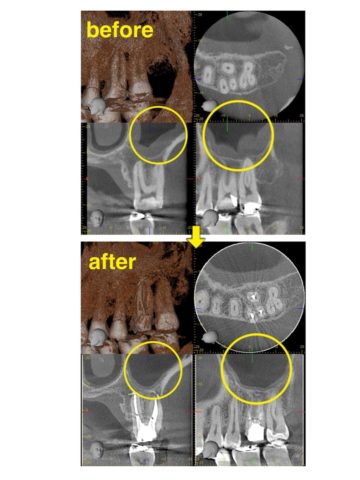

上顎洞炎と根尖病変の関係について